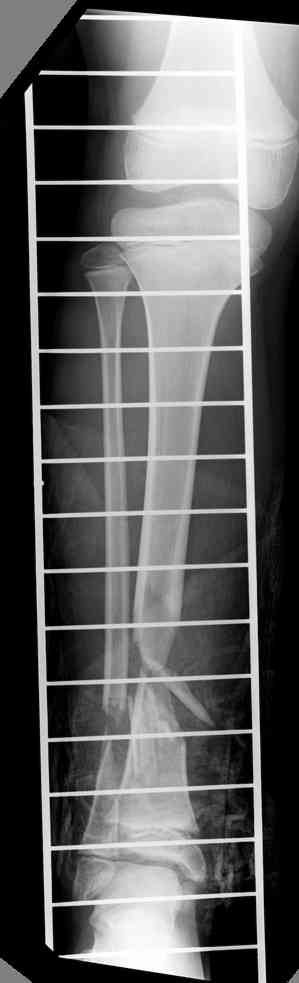

Another choice is simply perform shortening + posterior angulation with Ilizarov or TSF , than gradual correction of the angulation.After all apply third ring on the proximal tibia and start lengthening.

We had recently similar case in 14 years old boy with 45 mm bone defect after open tibial fracture.Boy doing excellent .This technique is not new, Sasha Lerner did it in Rambam , Rozbruch wrote also.

Another advantage of this techniqe is relaxation of soft tissue and possibility for closure even large defects of the skin.In your case I will apply ring on the foot and mid diaphysis of the tibia ,removal of the fibular plate,sindesmotic wire, and after correction of angulation on the proximal tibia.